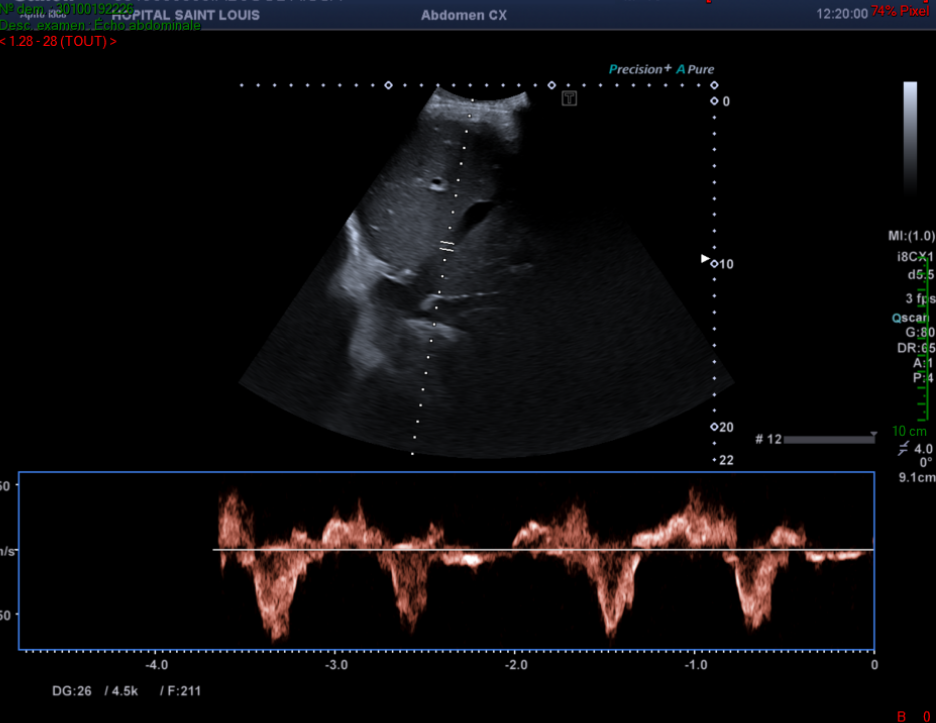

De plus, le flux du tronc porte attire son attention.

Il observe alors une alternance entre un flux hépatopète et hépatofuge au sein du tronc porte.

Un flux portal normal est dirigé vers le foie (hépatopète).

Un spectre normal du tronc porte est continu avec une légère pulsatilité liée à la décélération lors de l’inspiration.

Une importante pulsatilité est évocatrice d’une dysfonction ventriculaire droite et/ou d’une importante insuffisance tricuspide, signe indirect d’une hypertension artérielle pulmonaire.

Pulsatilité du tronc porte